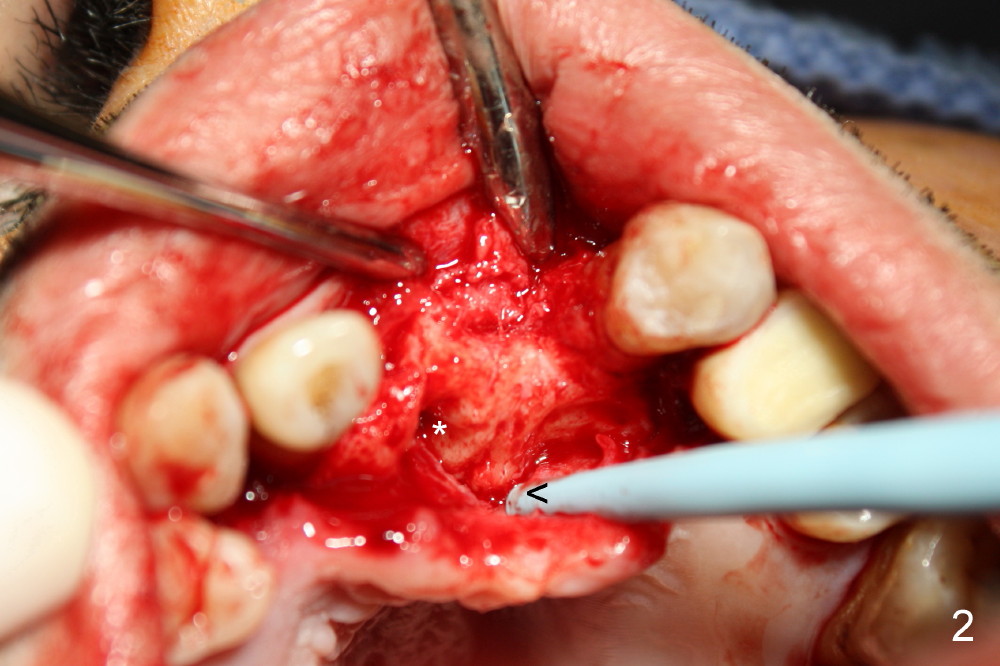

CBCT shows that the two mesiodens, esp. left one, are close to the palatal plate. After removal of the peridontally compromised tooth #8 and the pontic #9 (as compared to Fig.1), the palatal flap is raised to expose the left mesiodens (Fig.2 <; *: incisal foramen).